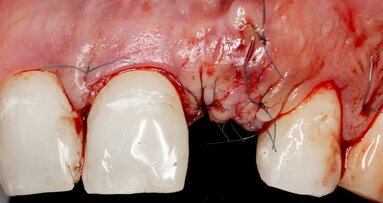

In the present case report, a new method that allows impression taking of implants inserted at a steep angle is presented. The use of implants for the ...